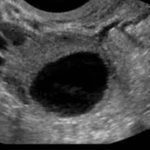

陈凤林教授指出:不排卵原因多种多样,但表现都一样,不管是自然周期,还是药物促排卵,都有一部分人卵泡发育到超过2cm后仍然不排出,继续增长,甚至超过4-6cm,个别的到了下个月经周期仍然没有排卵,医学上称为黄素化卵泡不破裂综合征(LUFs),为什么会有此种现象呢,有的人甚至一连几个月的监测都是如此,成为很多医患的不解之谜。

临床上不排卵主要有两类,一是黄素化卵泡不破裂综合征(LUFs), 另一类是排卵延迟,就是卵泡破裂的时间后延了,卵子过熟,两种情况都不会怀孕,但是哪种情况都可以用介入刺破助孕。